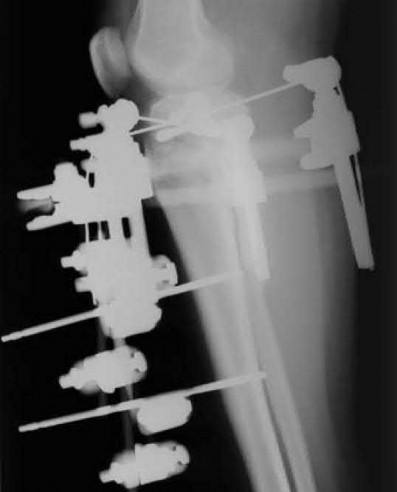

Question 19:

A 28-year-old male sustains a closed comminuted tibial shaft fracture. Two hours post-injury, he develops severe leg pain unyielding to narcotics. His blood pressure is 120/80 mmHg. Intracompartmental pressure monitoring is performed. Based on current guidelines, which measurement dictates an emergent 4-compartment fasciotomy?

Correct Answer: Delta pressure (Diastolic BP - Compartment Pressure) < 30 mmHg

Acute compartment syndrome is classically defined by tissue hypoperfusion. The absolute compartment pressure is less reliable than the differential pressure (Delta P). A Delta P (Diastolic Blood Pressure minus Compartment Pressure) of less than 30 mmHg is an absolute indication for emergency fasciotomy, as capillary perfusion gradient is lost when tissue pressure approaches the diastolic pressure.